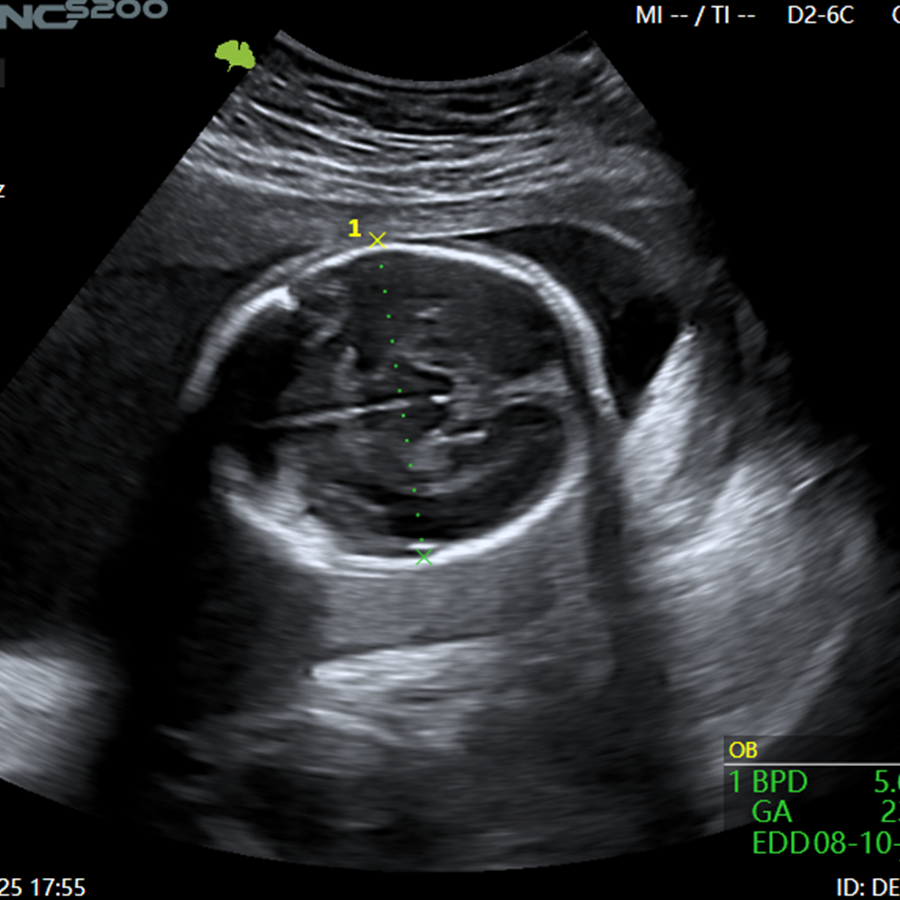

Ginecología

- Mediciones Automáticas

- VAim OB